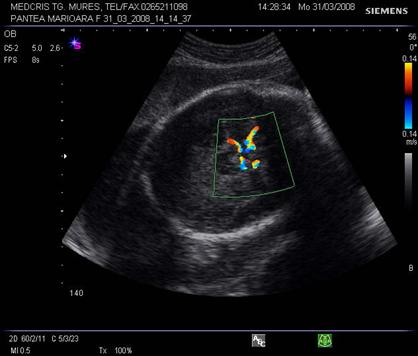

Doppler venos

Vena ombilicala - fluxul vascular poate fi apreciat in cordonul ombilical sau in abdomenul fetal. De obicei spectrul este monofazic daca fatul este in repaus motor si respirator.

Aspecte patologice ale spectrului Doppler constau in pulsatii venoase. Acestea par fiziologice, in timpul miscarilor respiratorii, iar patologice in trim. II si III in anomalii cardiace, aritmii sau insuficiente cardiace. Daca sunt asociate cu absenta fluxului end - diastolic in artera ombilicala, e vorba de insuficienta placentara si mortalitate de 50 - 60% [10,12].

Fig. nr. 327. Doppler cu pulsatii in vena ombilicala, in RCIU marcat la 34 sapt.